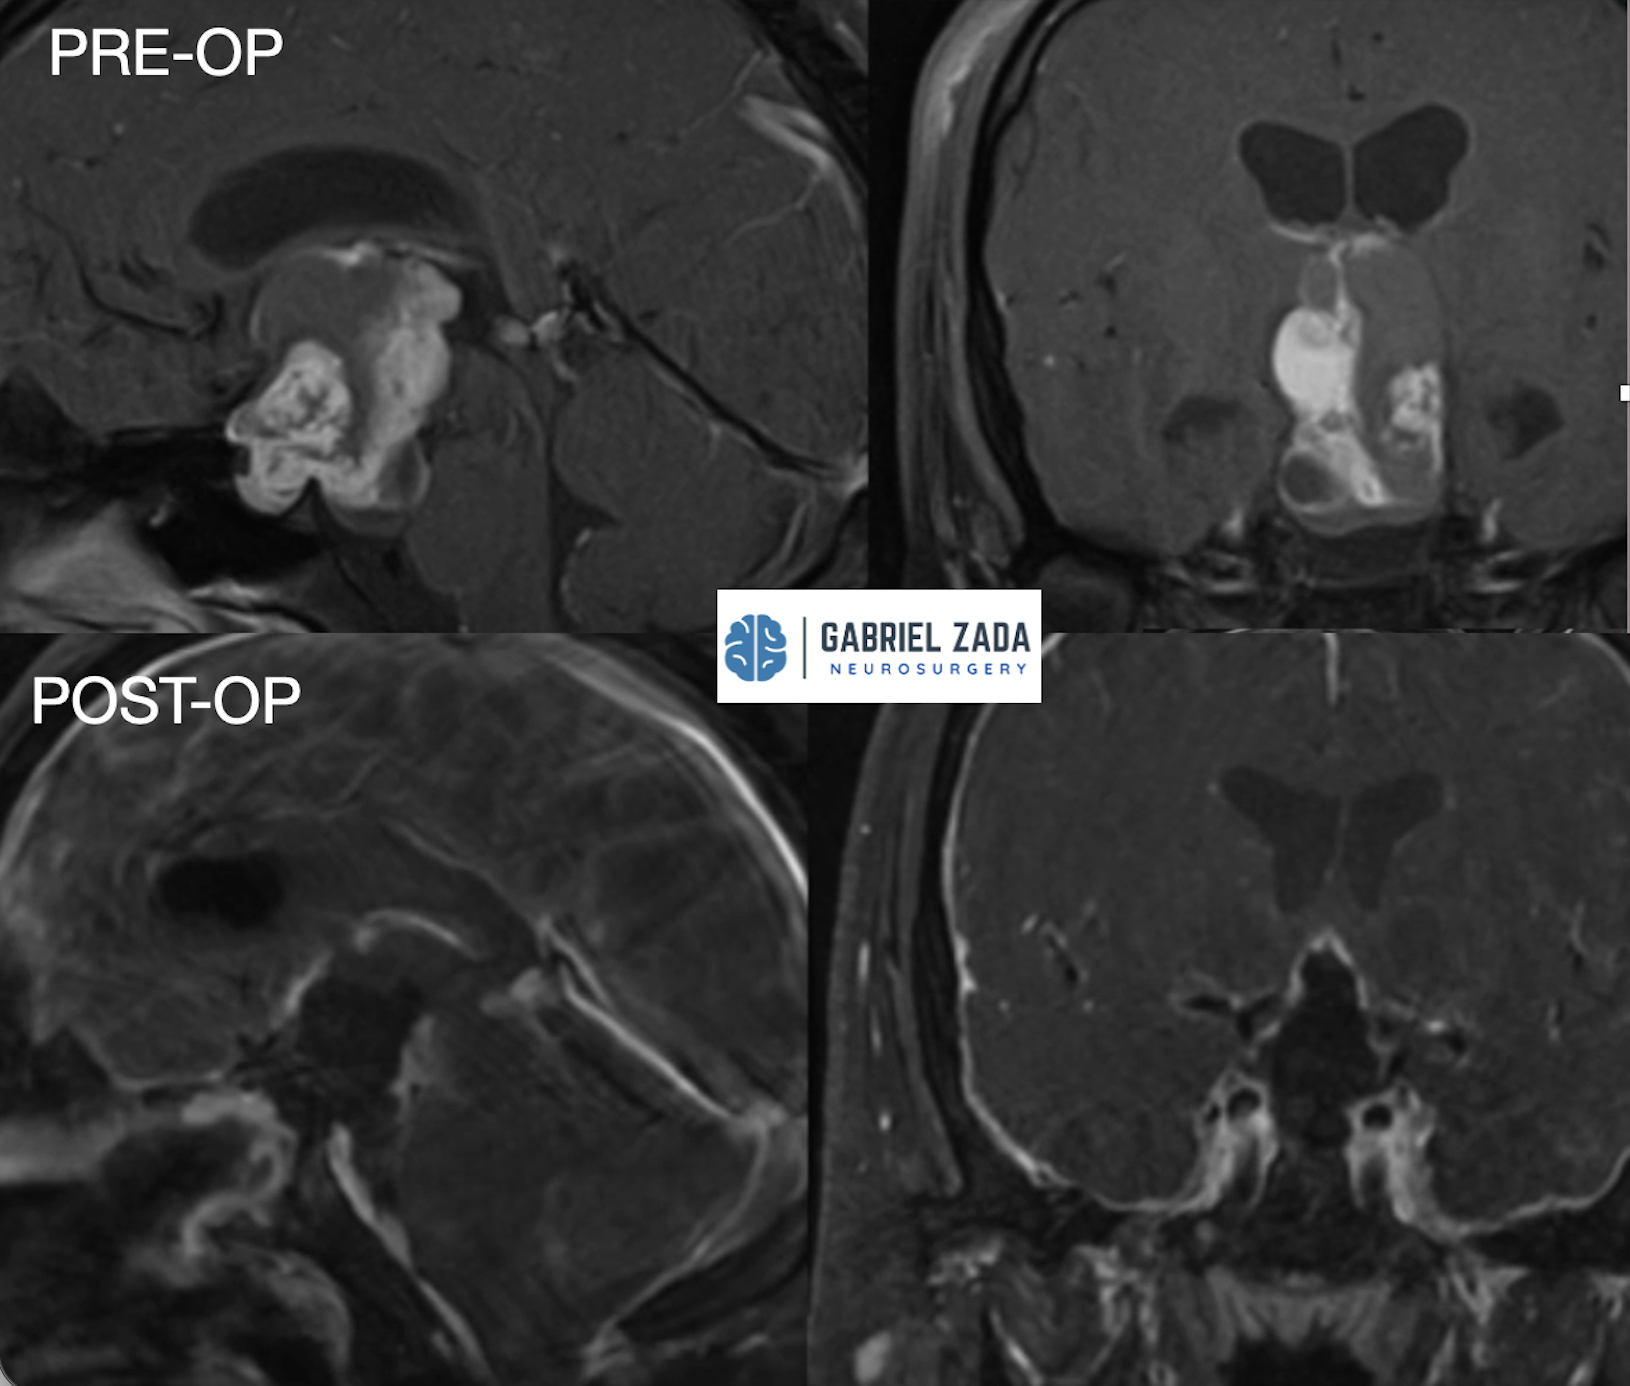

Craniopharyngioma treatment

• Complex tumors near the pituitary gland that require specialized neurosurgical expertise.